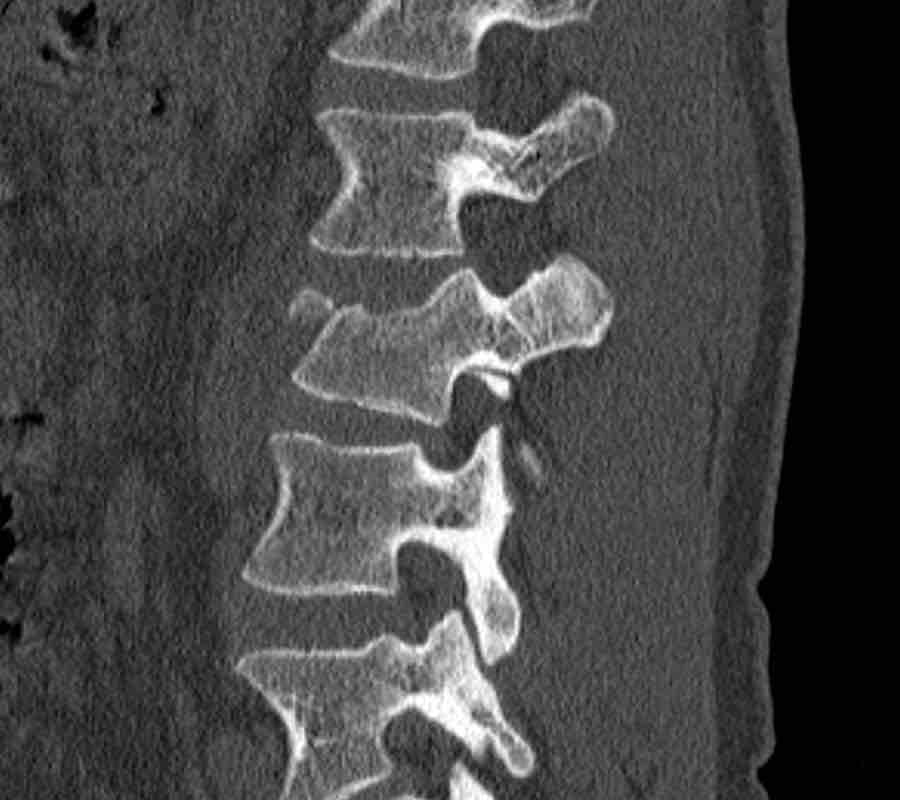

What is the highest AO-type of injury?

Findings

- No C or B injury.

- Fractures of the vertebral body with involvement of both endplates (1+1 points) and posterior wall (2 points).

- In the coronal plane, a sagittal course of the fracture is seen, which is common in burst fractures.

- Bulging of the posterior wall without any other signs of dislocation is the result of the burst fracture.

Therefore no C injury.

Conclusion

Injury type A4

Here more examples of typical burst injuries.

Due to the axial force, the vertebral body is ‘split in half’, therefore a sagittal course of the fracture is common.

Therefore a fracture through the posterior osseous structures is possible in some type A injuries and should not always be regarded as a posterior distraction injury.

This can be confusing sometimes.